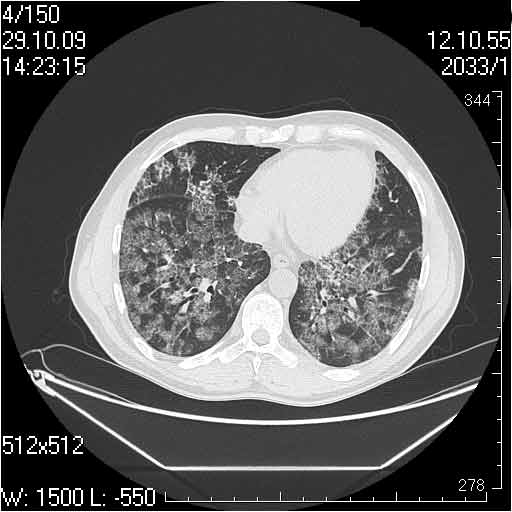

Случай №1

Женщина 50 лет.

Случай 1: изменения характерны для интерстициальной пневмонии (IIP/UIP idiopathic interstitial pneumonia/usual interstitial pneumonia); говорить о конкретной форме без открытой биопсии затруднительно.